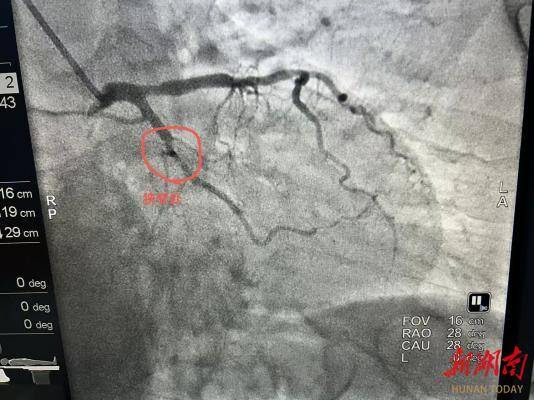

2. 适配特殊病变场景:像影像中这类局限性的血管狭窄,或是支架内再狭窄、小血管病变、分叉病变等情况,药物球囊能精准处理病变部位,避免了复杂病变下支架植入的局限性,也降低了多支架叠加的风险。

从影像看治疗效果:

“打通河道”且不留痕迹

此次治疗的造影对比极具说服力:术前狭窄处血管血流受阻,心肌供血不足,患者可能出现心绞痛等症状;药物球囊扩张后,狭窄处血管恢复正常管腔形态,血流顺畅通过,心肌缺血问题得到解决。更重要的是,血管内没有支架的“占位”,保留了血管的生理结构,为未来可能的再次治疗预留了更多空间。